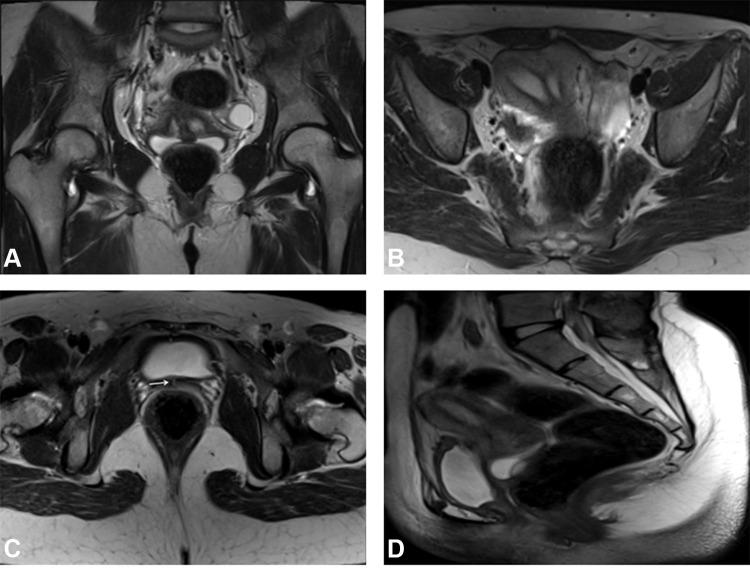

Variable mullerian anomalies were found among patients with multiple frequencies. Mullerian agenesis and hypoplasia were found in 12 patients (19%) and 16 patients (25%), respectively. Uterus didelphys was found in 5 patients (8%). Twelve (19%) patients had septate uterus, while 8 (12.5%) had a bicornuate anomaly. Unicornuate uterus was present in 7 patients (11%). Isolated vaginal anomaly was diagnosed in 4 patients (6%). Renal/urinary tract imaging was available for 27 (42%) patients, and accompanying urinary tract anomalies were noted in 10 of them (37%). Few ovarian and other extra-renal anomalies were observed.

MRI could efficiently delineate the mullerian anomalies regardless of their complexity. Most of these anomalies were more efficaciously categorized by the ESHRE and the new ASRM systems, compared to the originally widely used AFS system. The new ASRM classification was found to be more practical as it is a modification of the original AFS system, using drawings with clear descriptions instead of symbols. This is particularly helpful in the radiological era, saving time and effort.